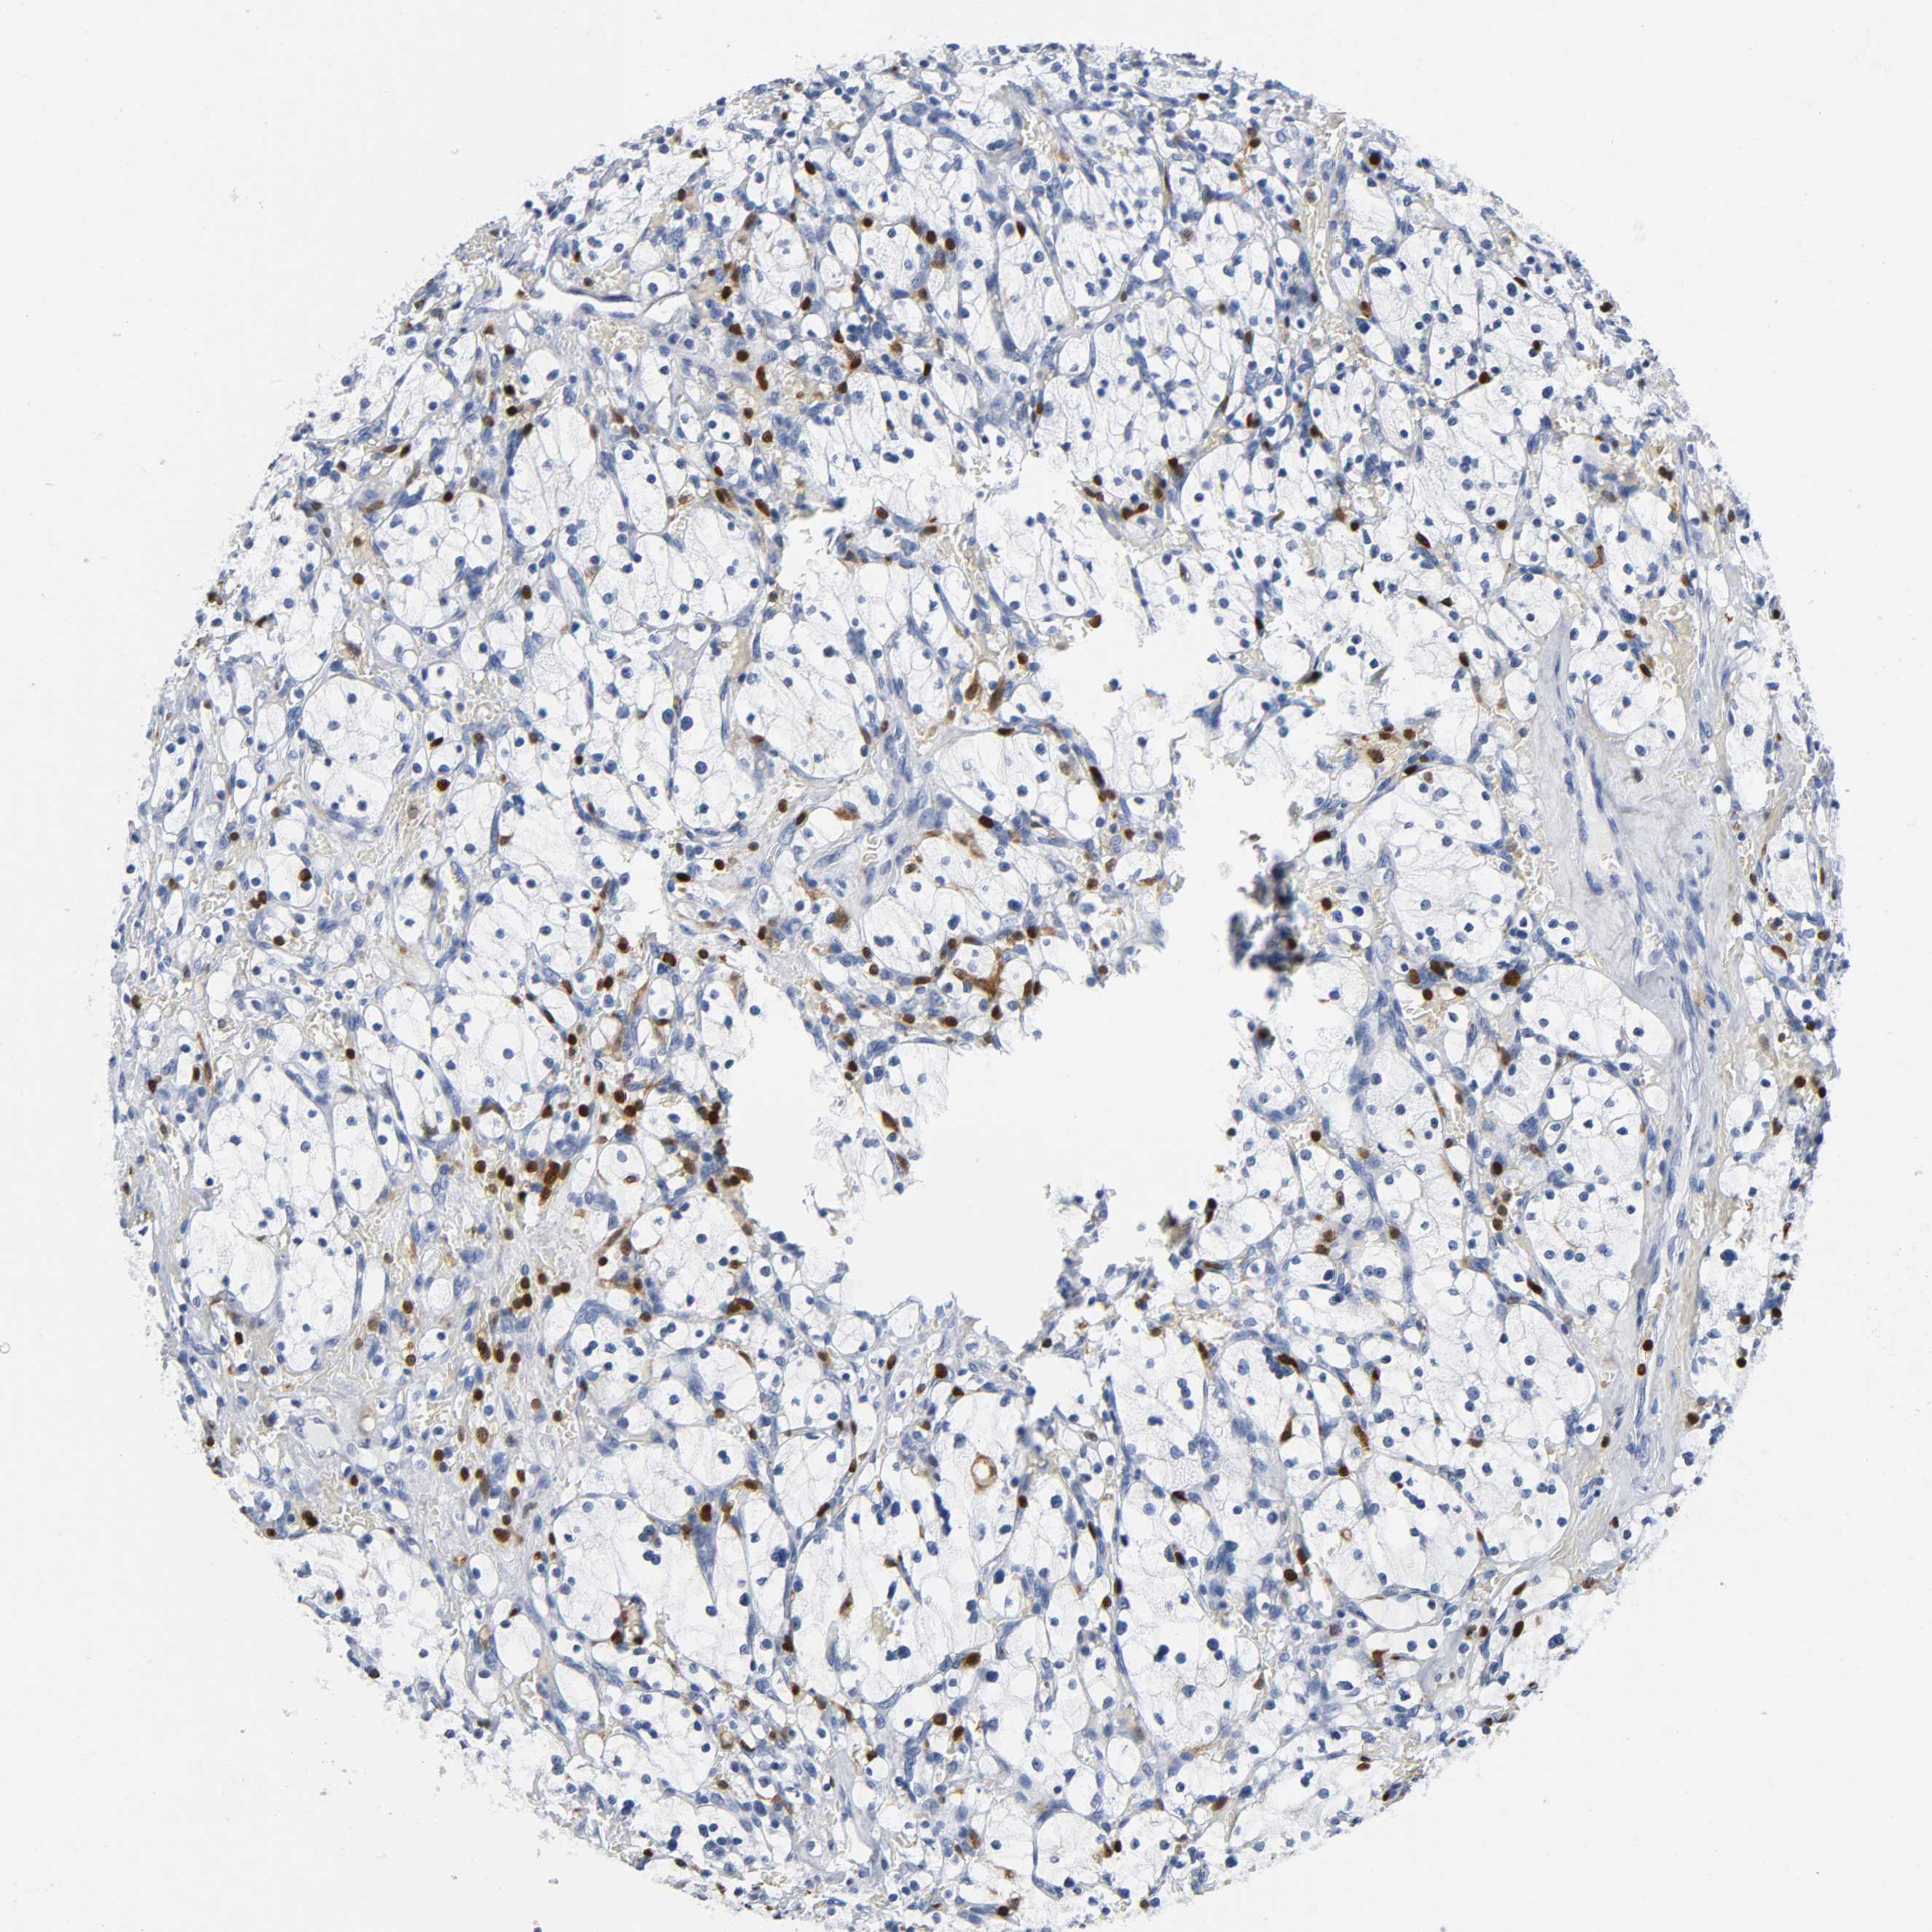

KIDNEY RENAL PAPILLARY CELL CARCINOMA (TCGA) - Interactive survival scatter ploti

The Survival Scatter plot shows the clinical status (i.e. dead or alive) for all individuals in the patient cohort, based on the same data that underlies the corresponding Kaplan-Meier plots. Patients that are alive at last time for follow-up are shown in blue and patients who have died during the study are shown in red.

The x-axis shows the expression levels (FPKM) of the investigated gene in the tumor tissue at the time of diagnosis. The y-axis shows the follow-up time after diagnosis (years). Both axes are complimented with kernel density curves demonstrating the data density over the axes. The top density plot shows the expression levels (FPKM) distribution among dead (red) and alive patients (blue). The right density plot shows the data density of the survived years of dead patients with high and low expression levels respectively, stratified using the cutoff indicated by the vertical dashed line through the Survival Scatter plot. This cutoff is automatically defined based on the FPKM cutoff that minimizes the p-score. The cutoff can be changed by dragging the vertical line or by entering a cutoff value in the square labeled "Current cut-off".

Under the Survival Scatter plot the p-score landscape (black curve; left axis) is shown together with dead median separation (red curve; right axis). Dead median separation is the difference in median mRNA expression between patients who have died with high and low expression, respectively. It is calculated as follows: median FPKM expression of dead patients with high expression - median FPKM expression of dead patients with low expression. This is intended to aid the user in visually exploring custom cutoffs and the associated p-scores and dead median separation.

Individual patient data is displayed and can be filtered by clicking on one or more of the category buttons on the top of the page. Categories describing expression level and patient information include: high, low, alive, dead, female, male and tumor stages. The scale of the x-axis can be toggled between linear and log-scale by clicking on the "x log" button. Mouse-over function shows TCGA ID, patient information and mRNA expression (FPKM) for each patient.

& Survival analysisi

Kaplan-Meier plots summarize results from analysis of correlation between mRNA expression level and patient survival. Patients were divided based on level of expression into one of the two groups "low" (under cut off) or "high" (over cut off). X-axis shows time for survival (years) and y-axis shows the probability of survival, where 1.0 corresponds to 100 percent.

DOK2 is not prognostic in Kidney Renal Papillary Cell Carcinoma (TCGA)